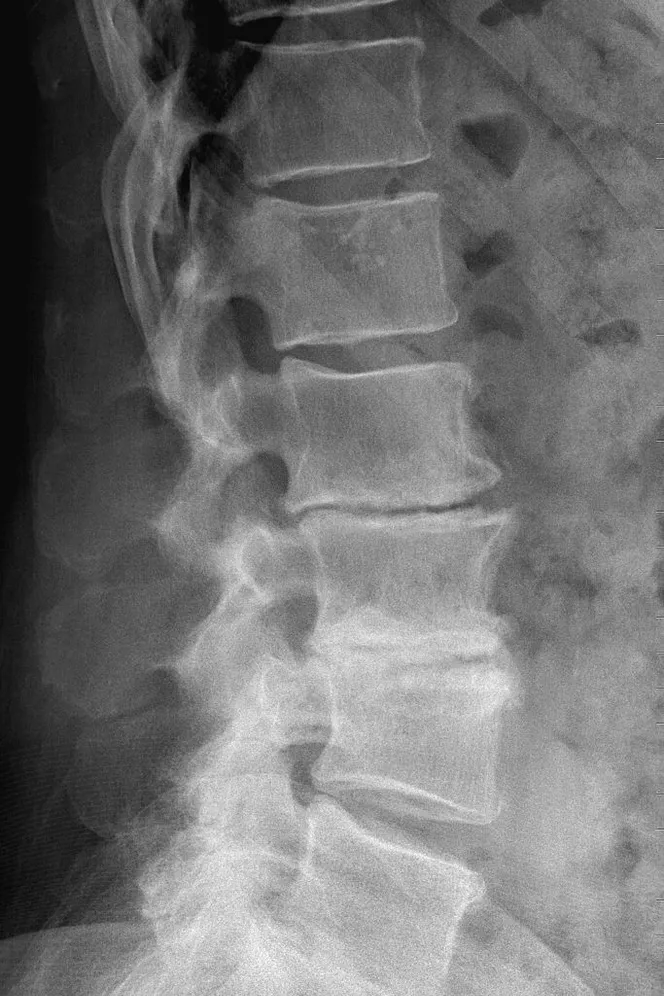

xray

Degenerative Disc Disease

Degenerative disc disease is not as much a disease as it is a name for the changes that can happen to the spine as we age. Our discs are made of a tough, rubbery exterior and a soft interior. They sit between the vertebrae to act as shock absorbers. As we age, the spinal discs begin to degenerate. This can cause herniated discs, bulging discs, spinal stenosis, and osteoarthritis.

The degeneration of spinal discs may cause no symptoms at all, and symptoms depend on each patient and the severity of their case. Pain may occur at the site of the affected disc in the back or neck. As the pain is often caused by compressed nerves, this pain can also travel to other areas of the body like the buttocks, arms, and legs. Numbness and tingling in the arms and legs may also be experienced. Pain can range from mild to severe and debilitating.

As mentioned previously, our spines can degenerate as a natural part of aging. Tears in the tougher outer layer of the disc are common as we grow older. and when the discs begin to lose fluid, they become smaller and less flexible. In addition to aging, other factors that may come into play, including obesity, smoking, repeated physical work, and injury.

Pain caused by degeneration is often treated with hot or cold packs and an anti inflammatory medication. When disc degeneration causes problems like herniated or bulging discs, spinal stenosis, or osteoarthritis, other forms of treatment may be beneficial. This may include physical therapy, stretching, and in some cases, surgery. While degenerative disc disease is a natural part of aging, there are things you can do to prevent pain and stay healthy. If you are experiencing frequent back or neck pain, be sure to visit our office for an examination so we can create a treatment plan for you.